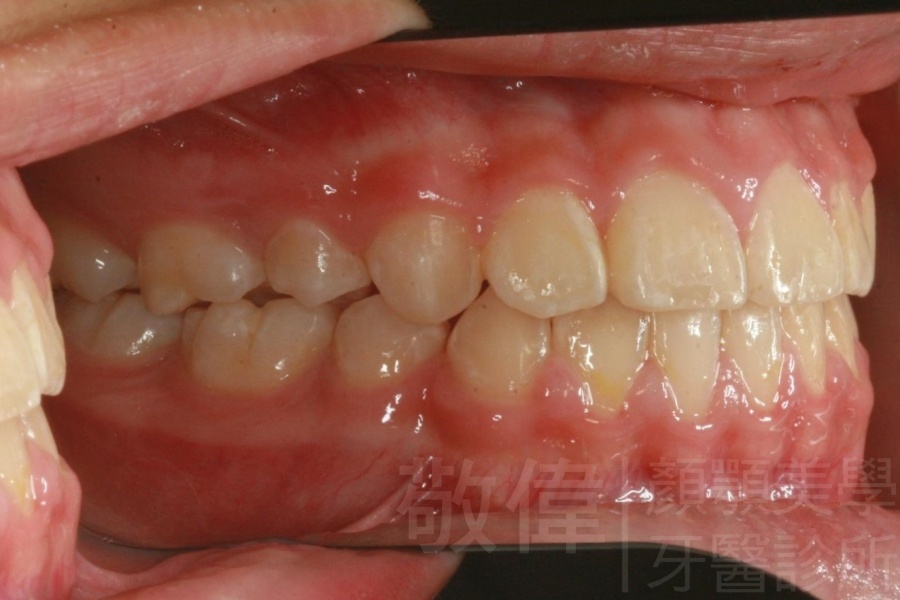

矯正前-右   矯正前-正   矯正前-左

矯正後-右   矯正後-正   矯正後-左

<個案說明>

上嘴唇微暴,透過矯正技術,改善了他的笑容還有臉型比例,看起來比之前合諧,現在在社會上與人相處充滿了自信,跟同事的相處也更為融洽,也會有比較大的機會站在比別人有利的位置。